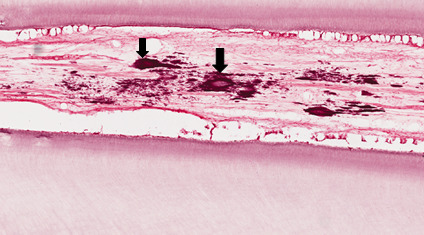

Corte transversal de um dente monorradicular apresentando dentina tubular, camada odontoblástica, polpa. Observar no interior do tecido conjuntivo pulpar a presença de calcificações patológicas (nódulos pulpares). Na periferia observa-se a degeneração dos odontoblastos ( atrofia reticular).

Degeneração Cálcica (Calcificação pulpar)